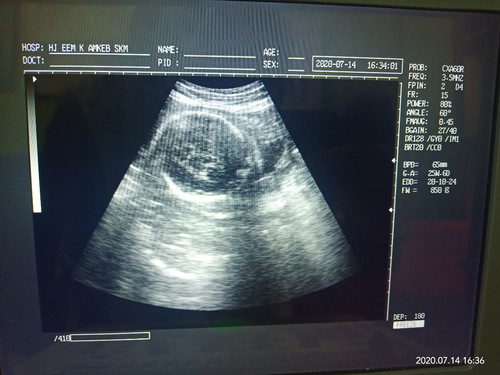

26 minggu

Ada yang sama bun ? 26 minggu, kepala masih di samping ..